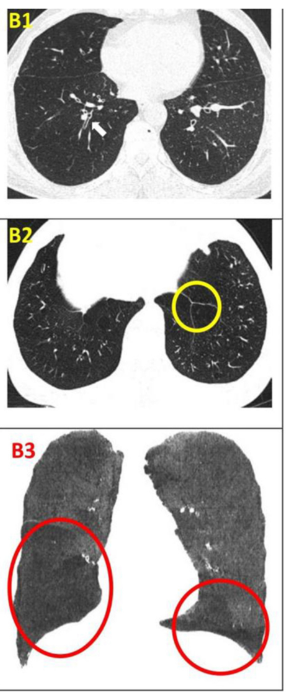

影像学检查改善:CT 值在 - 1000 至 - 951 比例有所下降,Class4( % ) 亦明显下降,故肺气肿较治疗前好转。附图为双源 CT 肺实质分析软件,深蓝色表示 CT 值在 -1000 至 - 951,治疗后较治疗前深蓝色面积明显缩小。

影像学检查:对于患者 #2902,定量分析显示基线时总体肺气肿面积比为 12.75%,移植后 24 周降至 10.02%。在患者 #8009 中,肺气肿面积比值从基线的 10.85% 下降到移植后 12 周的 9.08%。CT 图像的三维可视化显示,肺气肿的减轻在下叶比在上叶更明显。

影像学检查:随访12个月时,定量胸部CT扫描示患者吸入总肺容积略有增加,肺气肿指数无明显变化。支气管壁厚度(WT)的变化以WT、壁面积(WA)及WA百分比(%WA)的减少,以及支气管内径(ID)和管腔面积(LA)的增大来评估。

干细胞治疗一年后,双肺RB1和RB10的WT均减少,LA增加(粗体指数)。